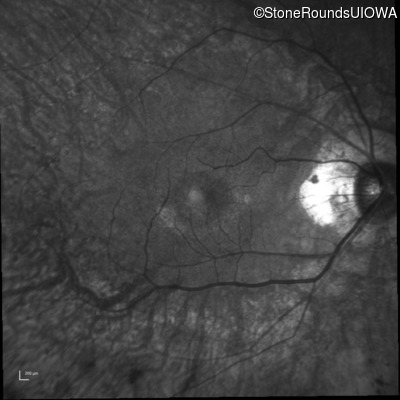

Visit at age: 58 years

Infrared Fundus Photograph - Left - 20/20 -2

Exemplar